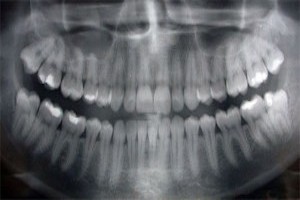

Panoramic X-Rays

Panoramic X-rays allow us to take a full-width image of your entire jaw, allowing us to see your full mouth in one picture. They are valuable for assessing the growth of adult and wisdom teeth, placing dental implants, and assessing bone health.